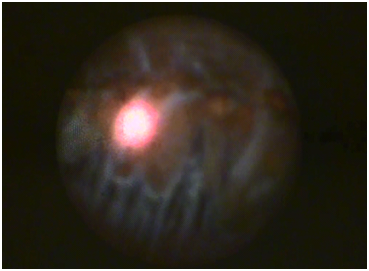

Indications for performing the surgery are progression of glaucoma on maximum tolerated topical treatment with co-existing cataract inability to tolerate or instil glaucoma drops (elderly,tremor,dementia,arthritis etc) and co-existing cataract. The endo-cyclophotocoagulation is usually performed towards the end of the procedure either after insertion of the IOL or immediately prior to this. The most important aspect to bear in mind whilst performing the procedure is to avoid any contact with the iris as this usually results in a very brisk uveitis with fibrin dump postoperatively. Always ensure the sulcus remains fully inflated with visco-elastic and always remove all the visco-elastic from the bag first at the end of lens implantation as this will allow a much fuller view and treatment area of the ciliary processes. The main corneal incision is used to insert the laser probe into the anterior chamber after inflating the ciliary sulcus with visco-elastic. The probe is advanced forward under the iris and pointing towards the ciliary processes. The laser, which is not in the visible spectrum, has a guiding Xe-Ne beam. The laser is set to ‘painting’ mode allowing a continuous ‘painting’ of the ciliary processes whilst the effect of the treatment is observed on a monitor adjacent to the operating table showing the view through the fiber optic video cable of the laser probe (Figure 1). The operating microscope is only used in order to visualize the insertion of the viscoelastic and a safe insertion of the laser probe. The effect of the laser on the ciliary bodies is a visual change in the shape and colour of the processes. They shrink and turn from a brownish colour to white in eyes without pseudo-exfoliation (PXE) (Figure 2). There is a marked difference both in the visual appearance as well as the reaction to the laser in patients with PXE with minimal shrinking and colour change (Figure 3). The author enlarges the side port used in the phacoemulsification to allow for a full 360 degrees treatment.

Figure 2 View of ciliary processes.

Figure 3 Note the iris, processes and zonules coated in pseudo exfoliative material.